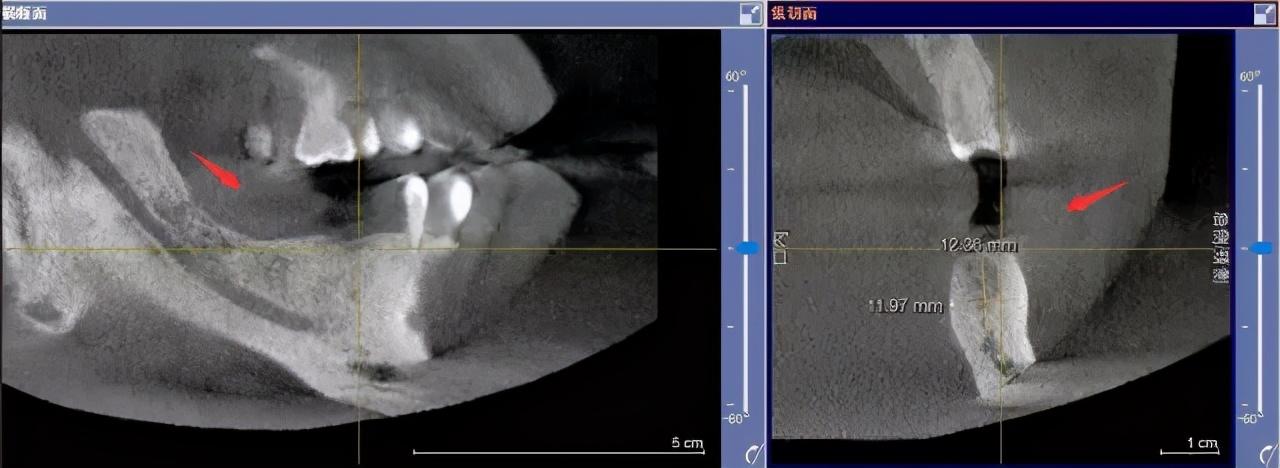

step1

先要做一個(gè)口腔全景片、頜骨CT等

醫(yī)生根據(jù)機(jī)器成像查看口腔的具體情況,

是否有炎癥、牙槽骨的密度、吸收狀況

以及鄰牙組織、牙體組織等。

注明:此數(shù)據(jù)僅作模擬,不是確切種植數(shù)據(jù)。

如果僅靠雙眼大致估測(cè)口內(nèi)數(shù)據(jù),是無(wú)法得到的高度、寬度的,也無(wú)法確認(rèn)骨頭吸收多少,是否需要植入骨粉。

對(duì)后期手術(shù)有一定的影響。

通過(guò)全景片可以“解剖”牙齒測(cè)量,適宜的種植角度也可確定,健康有保障。